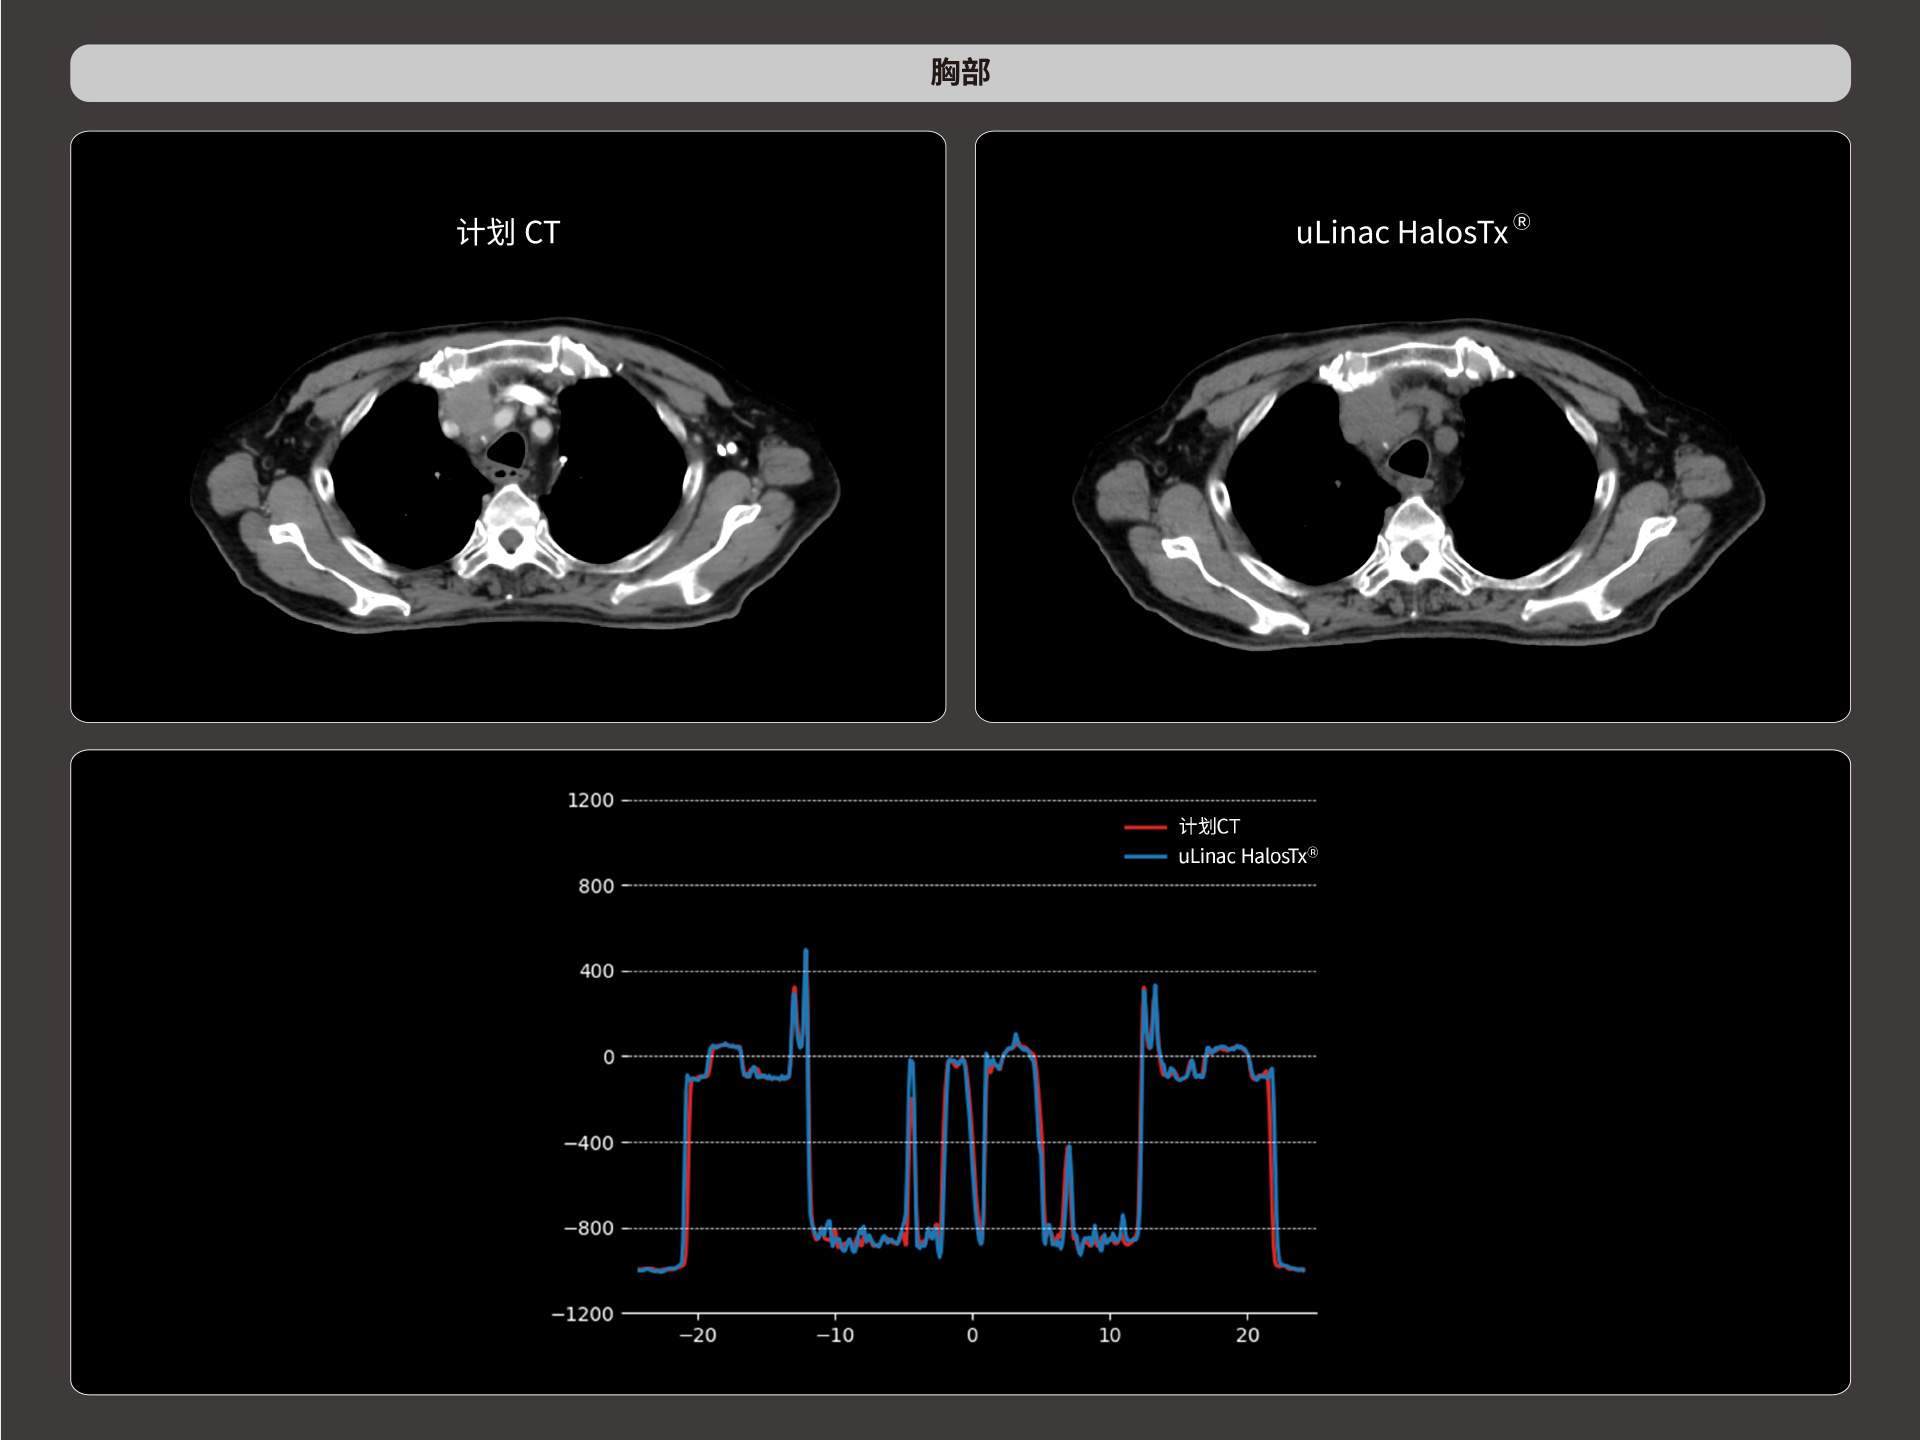

扇形束成像,极低散射,媲美CT-sim的影像品质

3mm @ 0.3% 高软组织对比度,0.55mm薄层扫描,精确鉴别肿瘤靶区边界

精准CT值,完美满足勾画、剂量计算要求

从数据源头提升图像质量,高清呈现细微变化,全面精进机载影像实力

提供传统 的CT 模拟机所一致的HU值精度(±10HU)

HU金标准